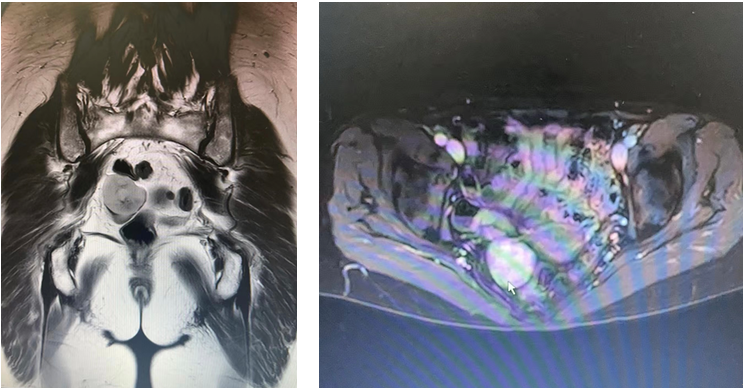

患者为62岁女性,3天前体检查腹部B超提示盆腔实性占位,反复行妇科超声、超声造影检查,认为是肠道来源,外生型MT可能。遂转诊至消化内科专家门诊,行肠镜发现多发性结肠息肉,另外门诊磁共振考虑妇科来源可能?于是转诊至妇产科,妇产科综合以上检查考虑可能是盆腔孤立肿瘤或消化道来源可能,再次转诊至我科特约门诊。收入院后完善小肠CTA检查提示:小肠螺旋CT未见明显异常,子宫后方4.5*3.1cm实性占位,考虑卵巢来源,颗粒细胞瘤?经MDT讨论后初步考虑盆腔占位,拟行腹腔镜下盆腔病损切除术。

患者取改良截石位,置入Trocar,行腹腔镜探查见右下腹网膜粘连,余无殊。探查盆腔:两侧卵巢未见明显异常,距离回盲部100cm见一外生型肿瘤,大小约5*4cm,因重力作用垂于盆腔。取绕脐4cm切口进腹后,将肿瘤所在肠段提出体外,距离肿瘤两侧5cm处,侧侧吻合,切除肿瘤。术后病理:暂未出。